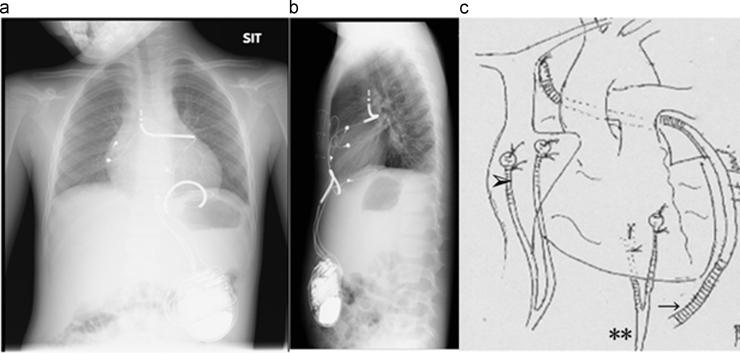

Epicardially placed implantable cardioverter-defibrillator for a child with congenital long QT syndrome.

A 7-year-old boy presented at our hospital with syncope. At birth, electrocardiography had shown a long QT interval with torsade de pointes (TdP). Congenital long QT syndrome (LQTS) had been diagnosed by genetic testing, and was successfully controlled with oral propranolol. At age 7, TdP had recurred with syncope. Electrocardiography revealed a prominent long QT interval with T-wave alternans. The propranolol dose was increased, but TdP remained uncontrolled. A cardioverter-defibrillator (ICD) was implanted epicardially, and TdP completely resolved with atrial pacing. We report this rare case of ICD implantation in a child with LQTS.

一名7岁男孩因晕厥前来我院就诊。出生时,心电图显示QT间期延长并伴有尖端扭转型室速(TdP)。基因检测诊断为先天性长QT综合征(LQTS),口服普萘洛尔后病情得到成功控制。7岁时,TdP再次发作并伴有晕厥。心电图显示QT间期显著延长并伴有T波交替。普萘洛尔剂量增加,但TdP仍未得到控制。遂在心外膜植入心脏复律除颤器(ICD),通过心房起搏后TdP完全消失。我们报告了这例在LQTS患儿中植入ICD的罕见病例。